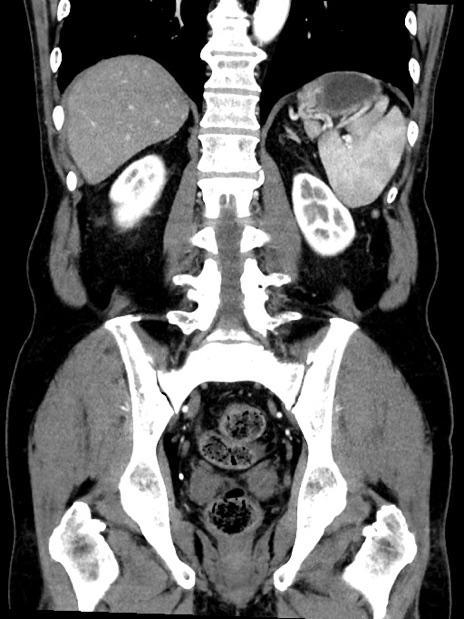

症例35(冠状断像)

【症例】70歳代 男性

【主訴】腹部膨満、嘔吐

【現病歴】昨日より腹部膨満感出現。本日増悪し、仙痛出現。嘔吐あり、受診。

【既往歴】糖尿病、胆摘後

【身体所見】BP 149/80mmHg、HR 74/min、BT 35.9℃、腹部:膨満、軟、圧痛なし。腸雑音減弱あり。上腹部正中切開瘢痕あり。

【データ】WBC 13500、CRP 1.72